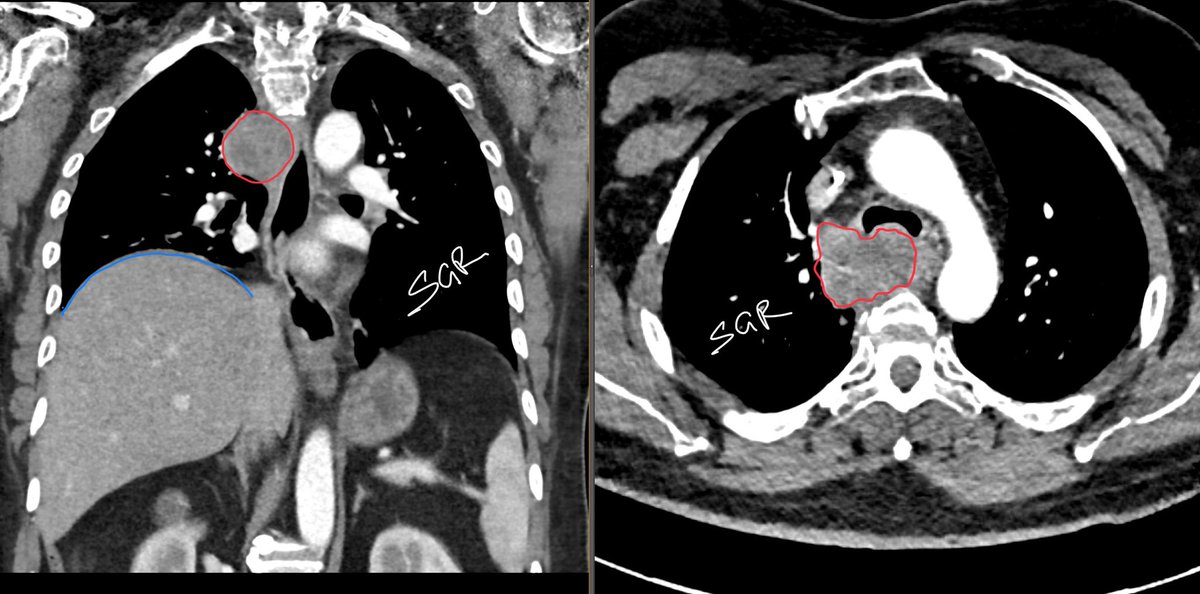

Right suprahilar/paratracheal opacity (red) with elevated right hemidiaphragm (blue), due to phrenic nerve palsy. CT to confirm. Port (yellow) was the clue for cancer. This was metastatic squamous cell CA. #medtwitter #radiology #oncology #radres #chestrad

Right suprahilar/paratracheal opacity (red) with elevated right hemidiaphragm (blue), due to phrenic nerve palsy. CT to confirm. Port (yellow) was the clue for cancer.

This was metastatic squamous cell CA. #medtwitter #radiology #oncology #radres #chestrad